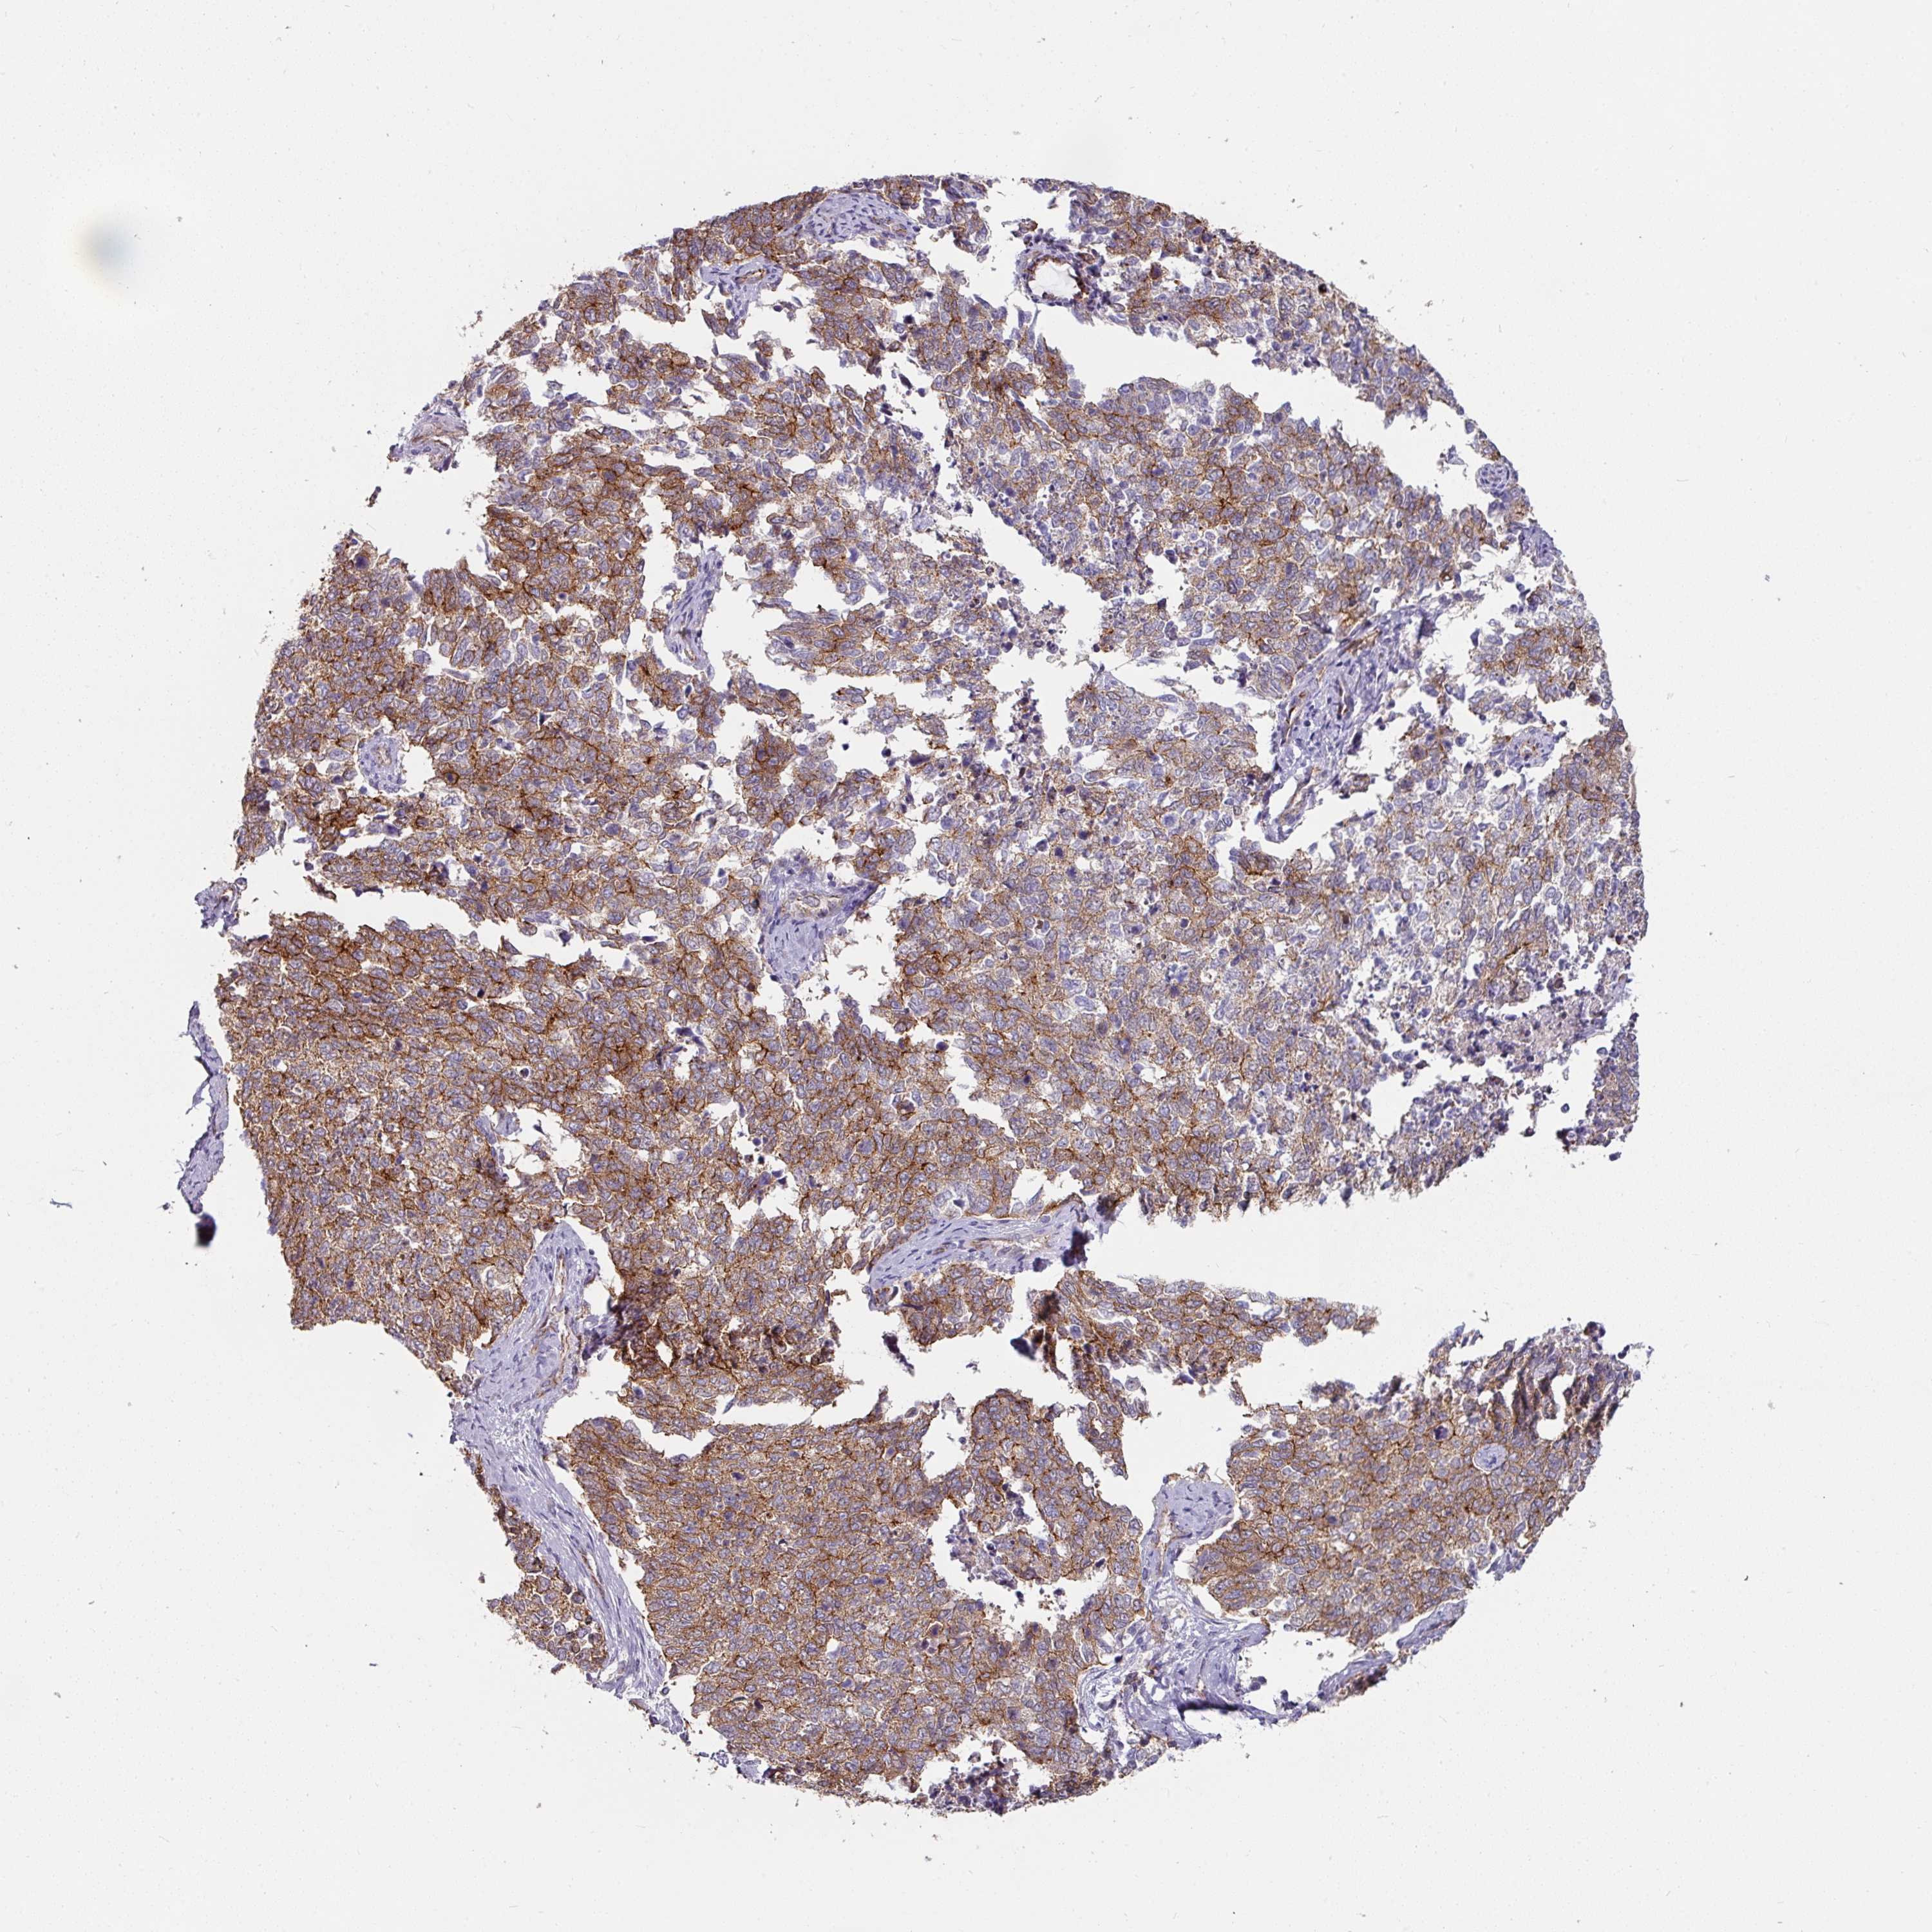

CERVICAL CANCER - Protein expressioni

A mouse-over function shows sample information and annotation data. Click on an image to view it in a full screen mode. Samples can be filtered based on level of antibody staining by selecting one or several of the following categories: high, medium, low and not detected. The assay and annotation is described here.

Note that samples used for immunohistochemistry by the Human Protein Atlas do not correspond to samples in the TCGA dataset.

Antibody stainingi

Antibody staining in the annotated cell types in the current human tissue is reported as not detected, low, medium, or high, based on conventional immunohistochemistry profiling in selected tissues. This score is based on the combination of the staining intensity and fraction of stained cells.

Each image is clickable and will lead to virtual microscopy that enables deeper exploration of all samples and also displays staining intensity scores, fraction scores and subcellular localization as well as patient and tissue information for each sample.

Antibody HPA032047

Antibody CAB002139

Adenocarcinoma, NOS